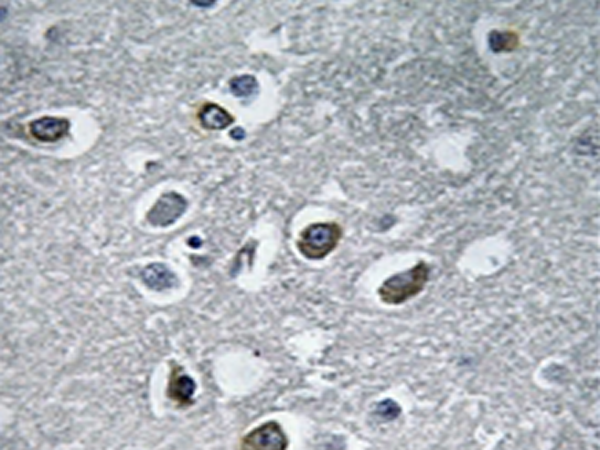

IHC positive control: |

Human brain tissue |

IHC Recommend dilution: |

50-100 |